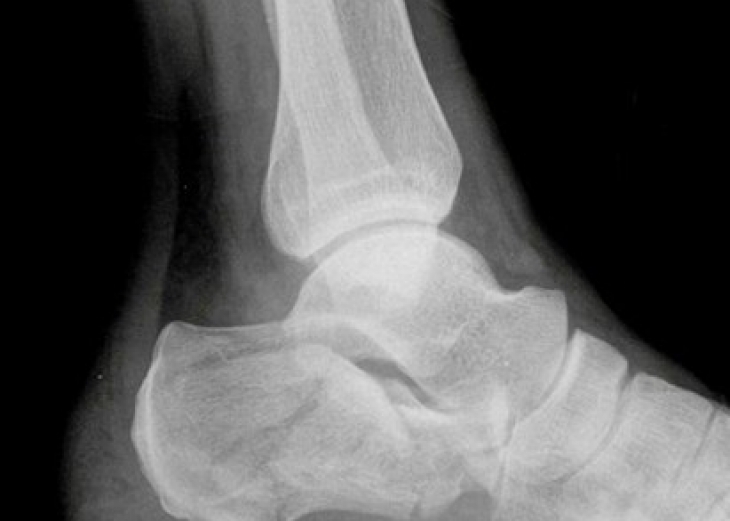

传统的切开复位内固定是治疗跟骨骨折的有效手段之一,并且也得到了国内外众多学者和专家的肯定,其中以传统的外侧“L”形切口入路切开复位内固定最为常见,几乎可以应对各种复杂类型的跟骨骨折...